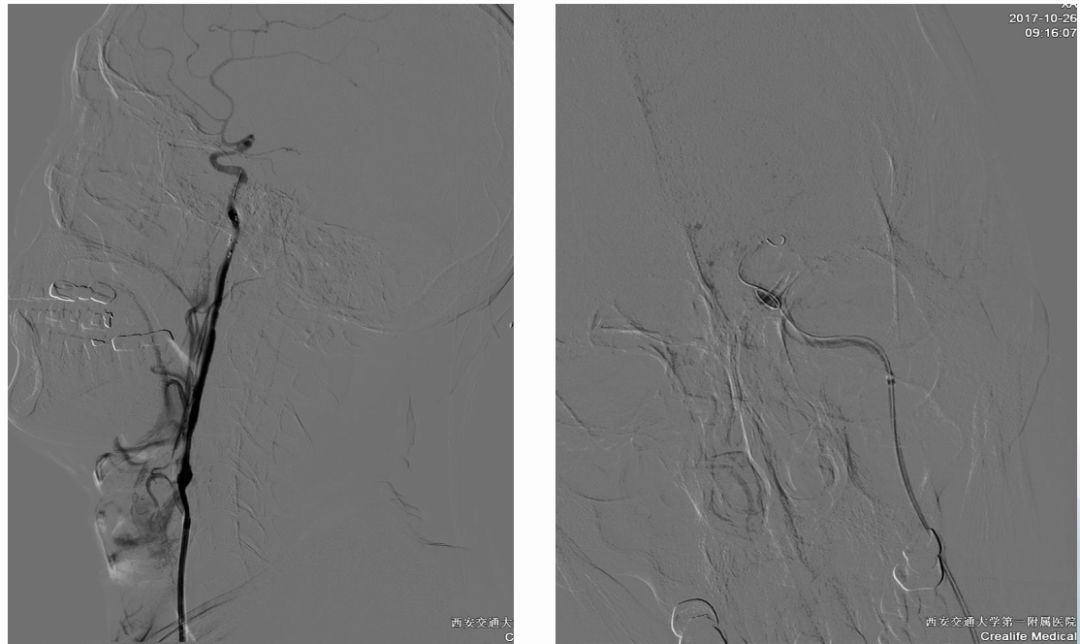

术前造影:

串联病变

双颈动脉支架

术后CT

24H

36H

45H

术前NIHSS评分 6分

术后24hNIHSS评分 1分

术后36hNIHSS评分 2分

术后45hNIHSS评分 22分